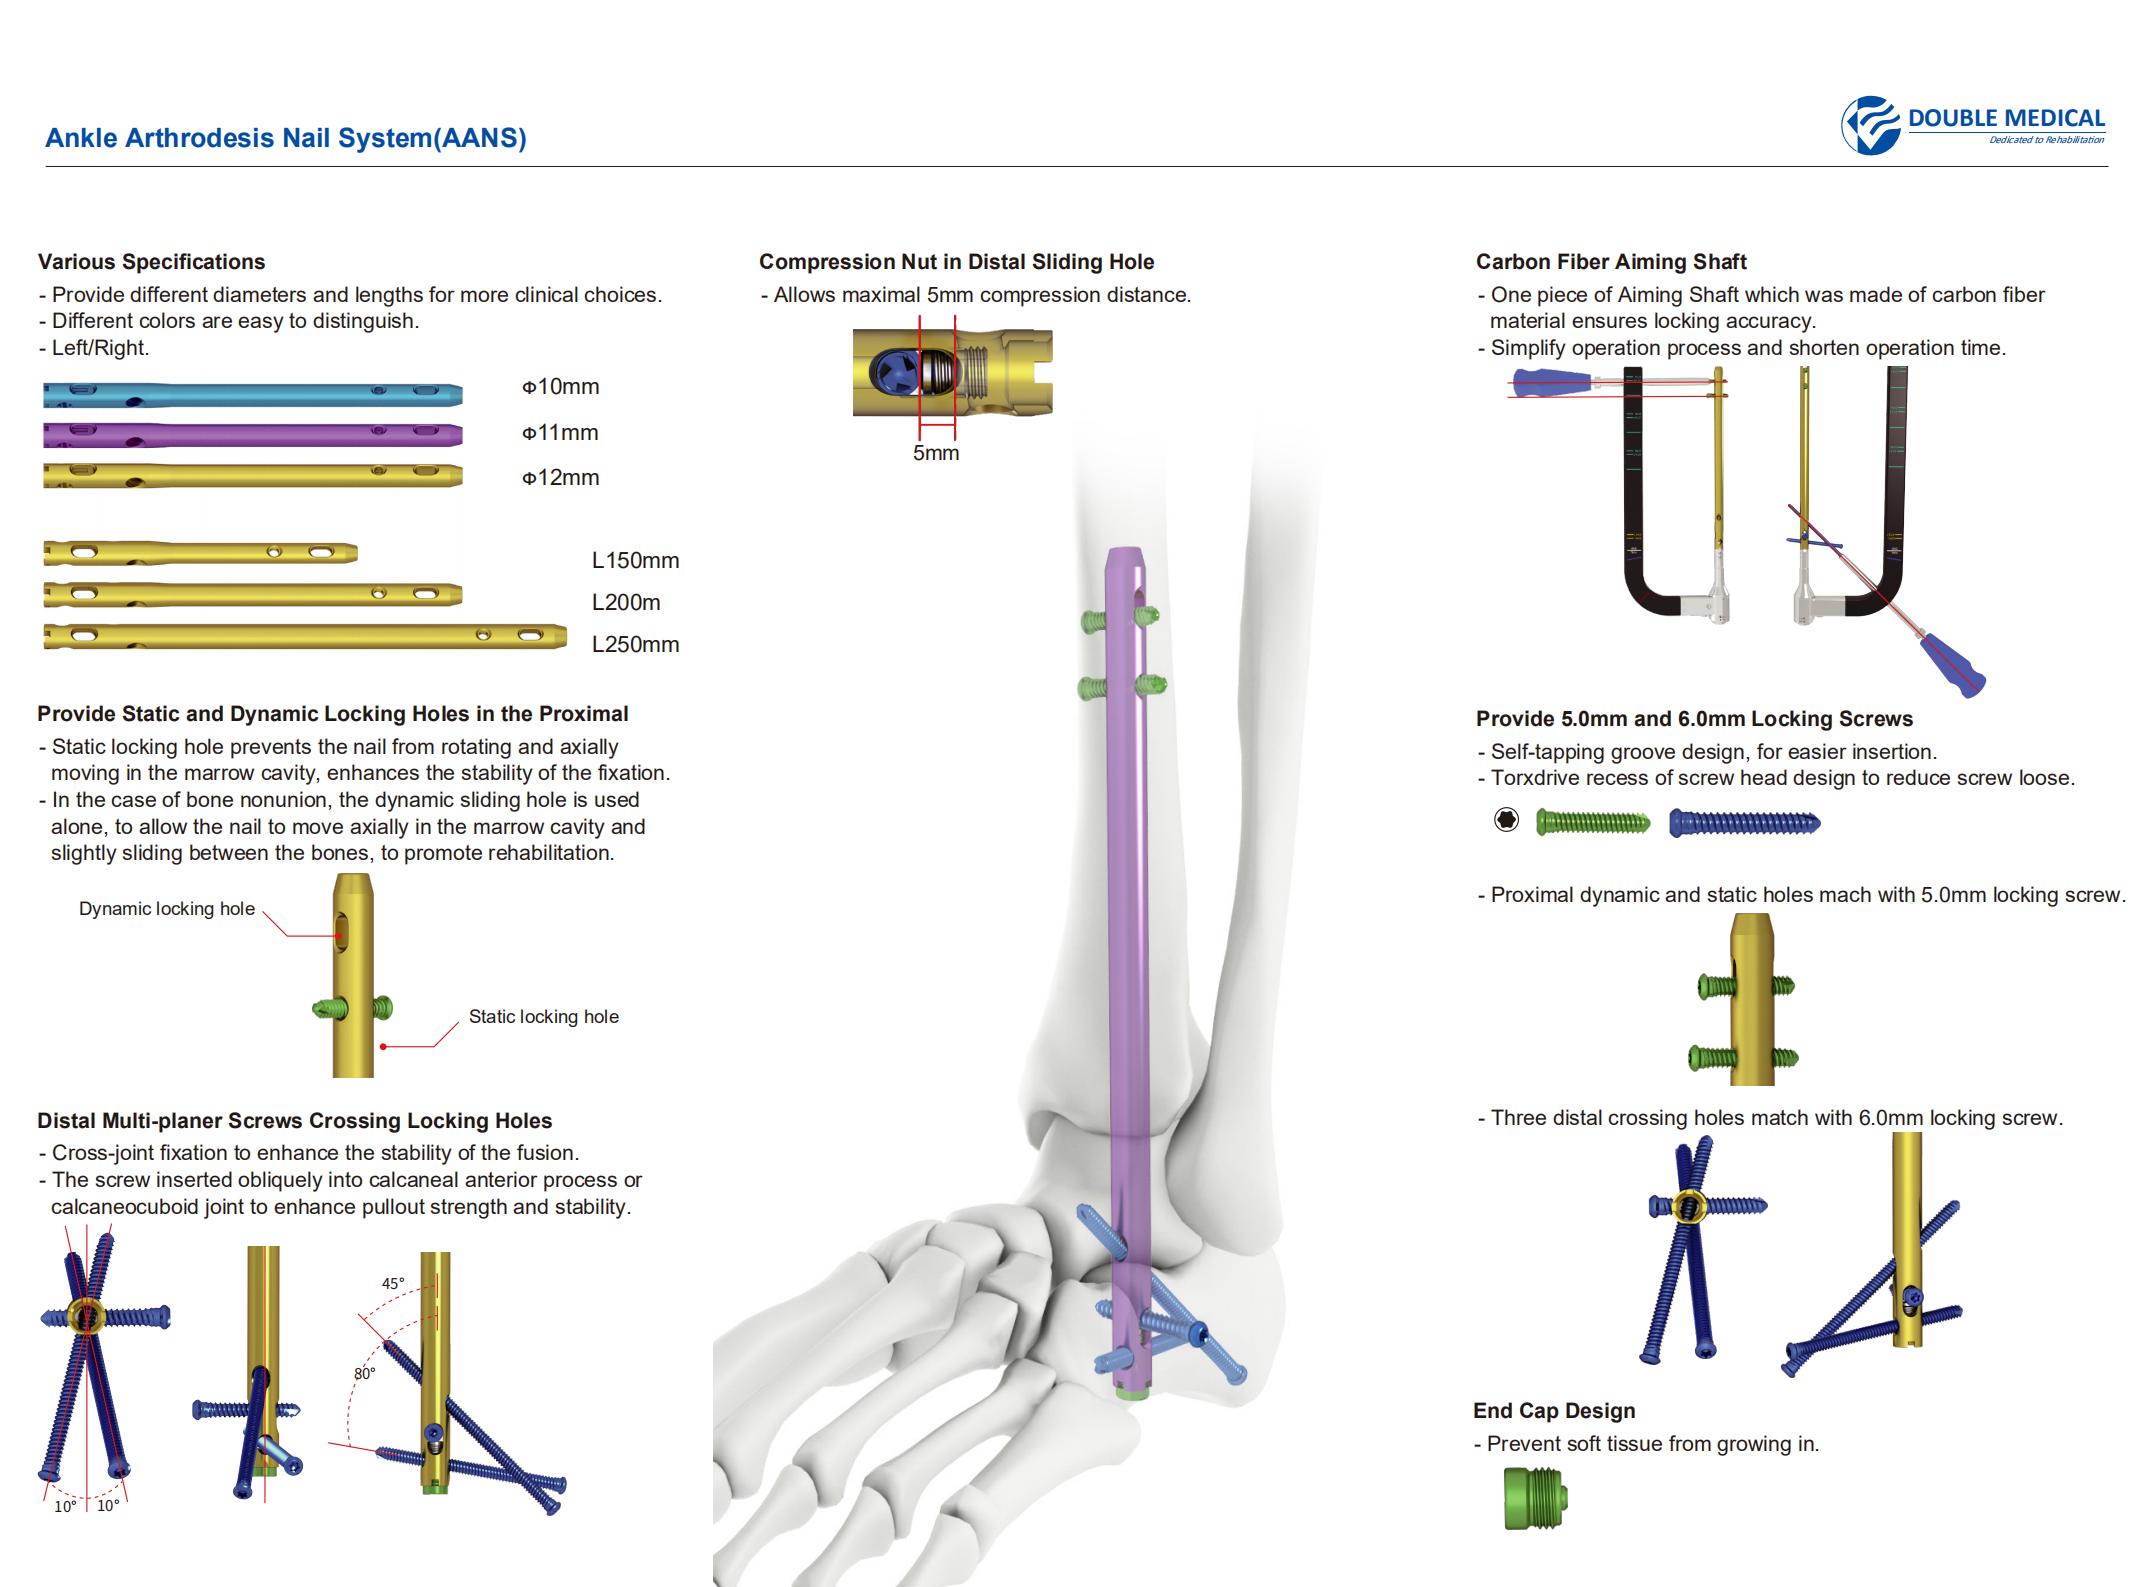

Clavo de artrodesis de tobillo:

- Proporcione diferentes diámetros y longitudes para más opciones clínicas.

- Los diferentes colores son fáciles de distinguir.

Tuerca de compresión en el orificio deslizante distal:

- El orificio deslizante distal permite una distancia máxima de compresión de 5 mm.

Orificios de bloqueo estáticos y dinámicos:

- Proporcione orificios de bloqueo estáticos y dinámicos en el proximal.

Tornillos distales para cepillado múltiple que cruzan los orificios de bloqueo:

- Fijación de articulaciones cruzadas para mejorar la estabilidad de la fusión.

- El tornillo se inserta oblicuamente en la apófisis anterior del calcáneo o en la articulación calcáneo-cuboidea para mejorar la fuerza y la estabilidad de extracción.

Eje direccional de carbono de cinco dedos:

- Una pieza de eje de puntería que está hecha de material de fibra de carbono garantiza la precisión de bloqueo.

- Simplifique el proceso de operación y acorte el tiempo de operación.

Tornillos de bloqueo:

- Diseño de ranura autorroscante para facilitar la inserción.

- Rebajo Torxdrive del diseño de la cabeza del tornillo para reducir el tornillo suelto.

- Agujeros proximales dinámicos y estáticos con tornillo de bloqueo de 5.0 mm.

- Tres orificios transversales distales coinciden con el tornillo de bloqueo de 6,0 mm.

Tapa final:

- Evita que los tejidos blandos crezcan.